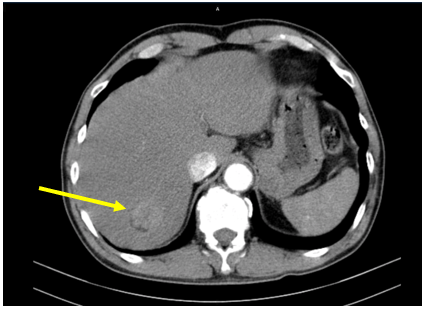

– Chụp cắt lớp vi tính bụng: (Tháng 12/2020) Hình ảnh khối ngấm thuốc gan phải: Nhu mô phân thùy VII có khối kích thước 37x35mm, ngấm thuốc thì động mạch, ngấm thêm vào trung tâm thì tĩnh mạch cửa, vùng trung tâm không thấy ngấm thuốc. Gan: Kích thước bình thường, bờ đều. Sỏi túi mật. Sỏi thận phải. Nang nhỏ thận trái.

Hình 1: Nhu mô phân thùy VII có khối kích thước 37x35mm, ngấm thuốc thì động mạch, ngấm thêm vào trung tâm thì tĩnh mạch cửa, vùng trung tâm không thấy ngấm thuốc. (mũi tên vàng)